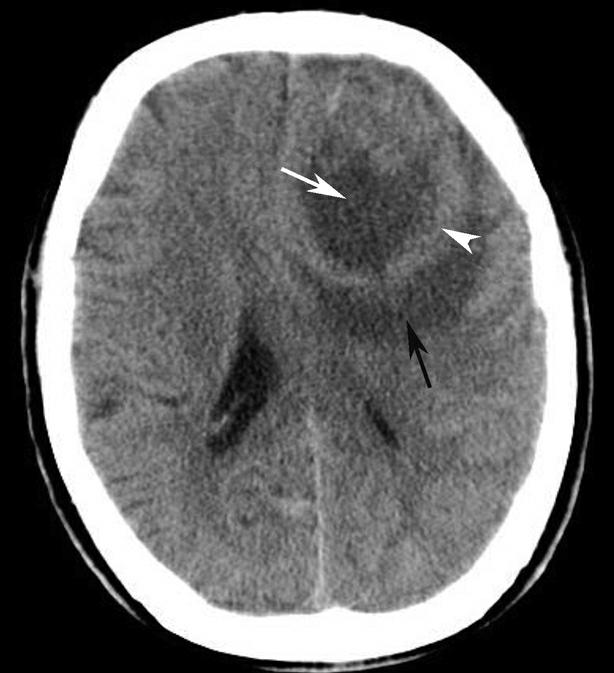

破裂孔、卵圆孔、棘孔及斜坡等均为重要的解剖结构,临床常见疾病如鼻咽癌常侵犯上述结构(图1-2-3)。颈静脉孔区较常见的肿瘤为颈静脉球瘤,常伴有颈静脉孔及其邻近骨质的破坏(图1-2-4)。

图1-2-3 鼻咽癌颅底骨质破坏

A.横断面;B.横断面(骨窗)

骨窗示左侧岩尖、斜坡、左侧蝶骨大翼骨质破坏、受侵(白箭),肿瘤经破裂孔侵入颅内(黑箭头)